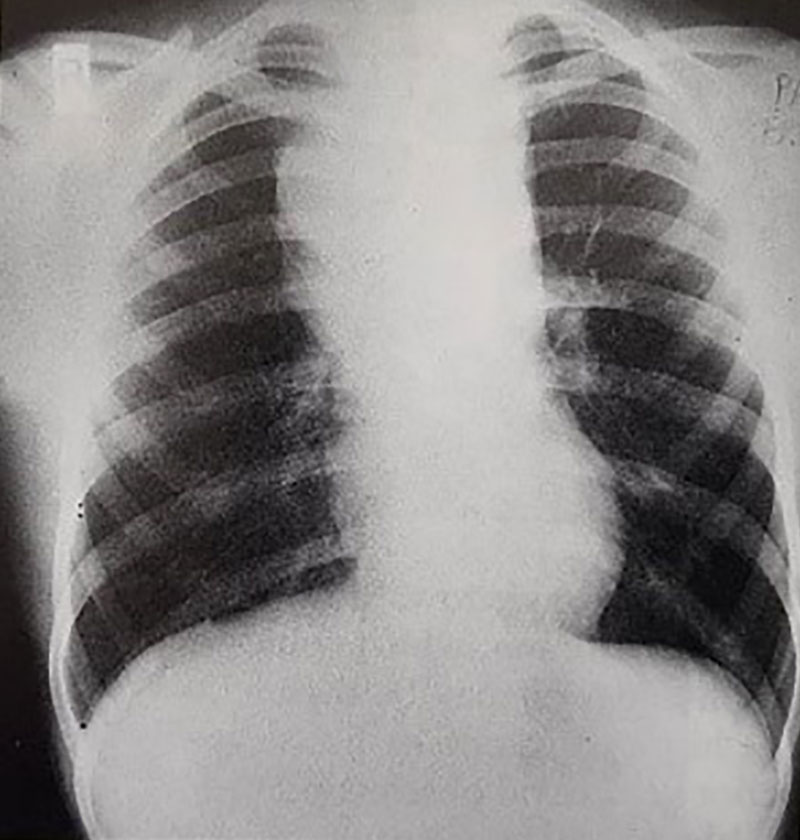

1. یافته های مشاهده شده در تصویر رادیوگرافی قفسه سینه شکل (56a) را تفسیر کنید.

تصویر رادیوگرافی قفسه، سینه تودهای را در ناحیه مدیاستن قدامی نشان میدهد که میتواند منشاء تیموسی یا ناشی از درگیری غدد لنفاوی باشد. سابقهی بالینی بیمار حاکی از بروز انسداد ورید اجوف فوقانی است.